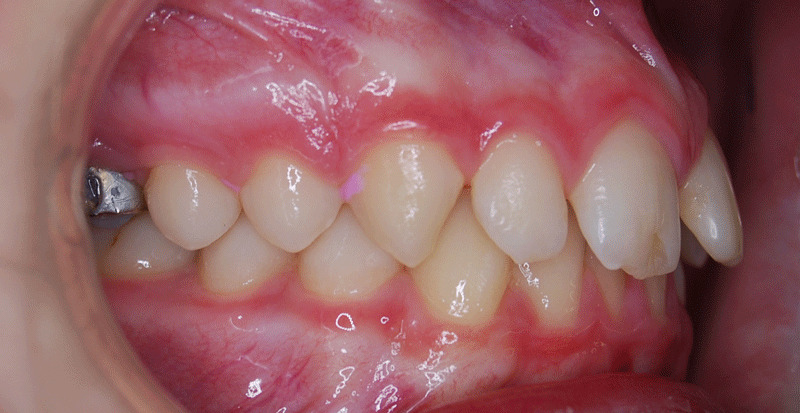

La sobremordida, lo que coloquialmente se conoce como mordida profunda, es un problema de maloclusión en que los dientes de arriba están adelantados y cubren excesivamente a los inferiores. Por lo tanto, podemos afirmar que existen distintos grados de sobremordida.

El overbite o sobremordida es la distancia entre el borde del incisivo central superior e inferior en sentido vertical. El overbite considerado normal tiene el incisivo superior sobrepasando aproximadamente 1/3 al incisivo inferior.

mordida profunda

El patrón braquifacial de crecimiento de la estructura facial (patrón de cara más ancha y corta que no alargada) es el que más se relaciona con la mordida profunda. Normalmente, estos patrones son maloclusiones de clase II, tanto dental como esquelética.